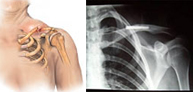

- Luxación acromioclavicular

Las luxaciones acromioclaviculares son producidas por traumatismos en el hombro y producen la separación entre la clavícula y el acromion. La fuerza deformante puede llegar al hombro de forma directa (impacto sobre hombro) o de forma indirecta tras caer sobre la mano con la extremidad extendida y transmitirse el impacto al hombro.

Son típicas de la segunda y tercera década de la vida y afectan casi siempre al sexo masculino por su mayor predisposición a los deportes de velocidad (motociclismo, automovilismo, ciclismo, esquí) y de contacto (karate, judo, tae-kwon-do).

En función de la separación entre los huesos que forman la articulación (acromion y clavícula) el tratamiento puede ser conservador o quirúrgico. Cuándo la separación es grande y la posibilidad de restauración por métodos conservadores es imposible proponemos una rápida y mínima intervención para la reparación articular definitiva.